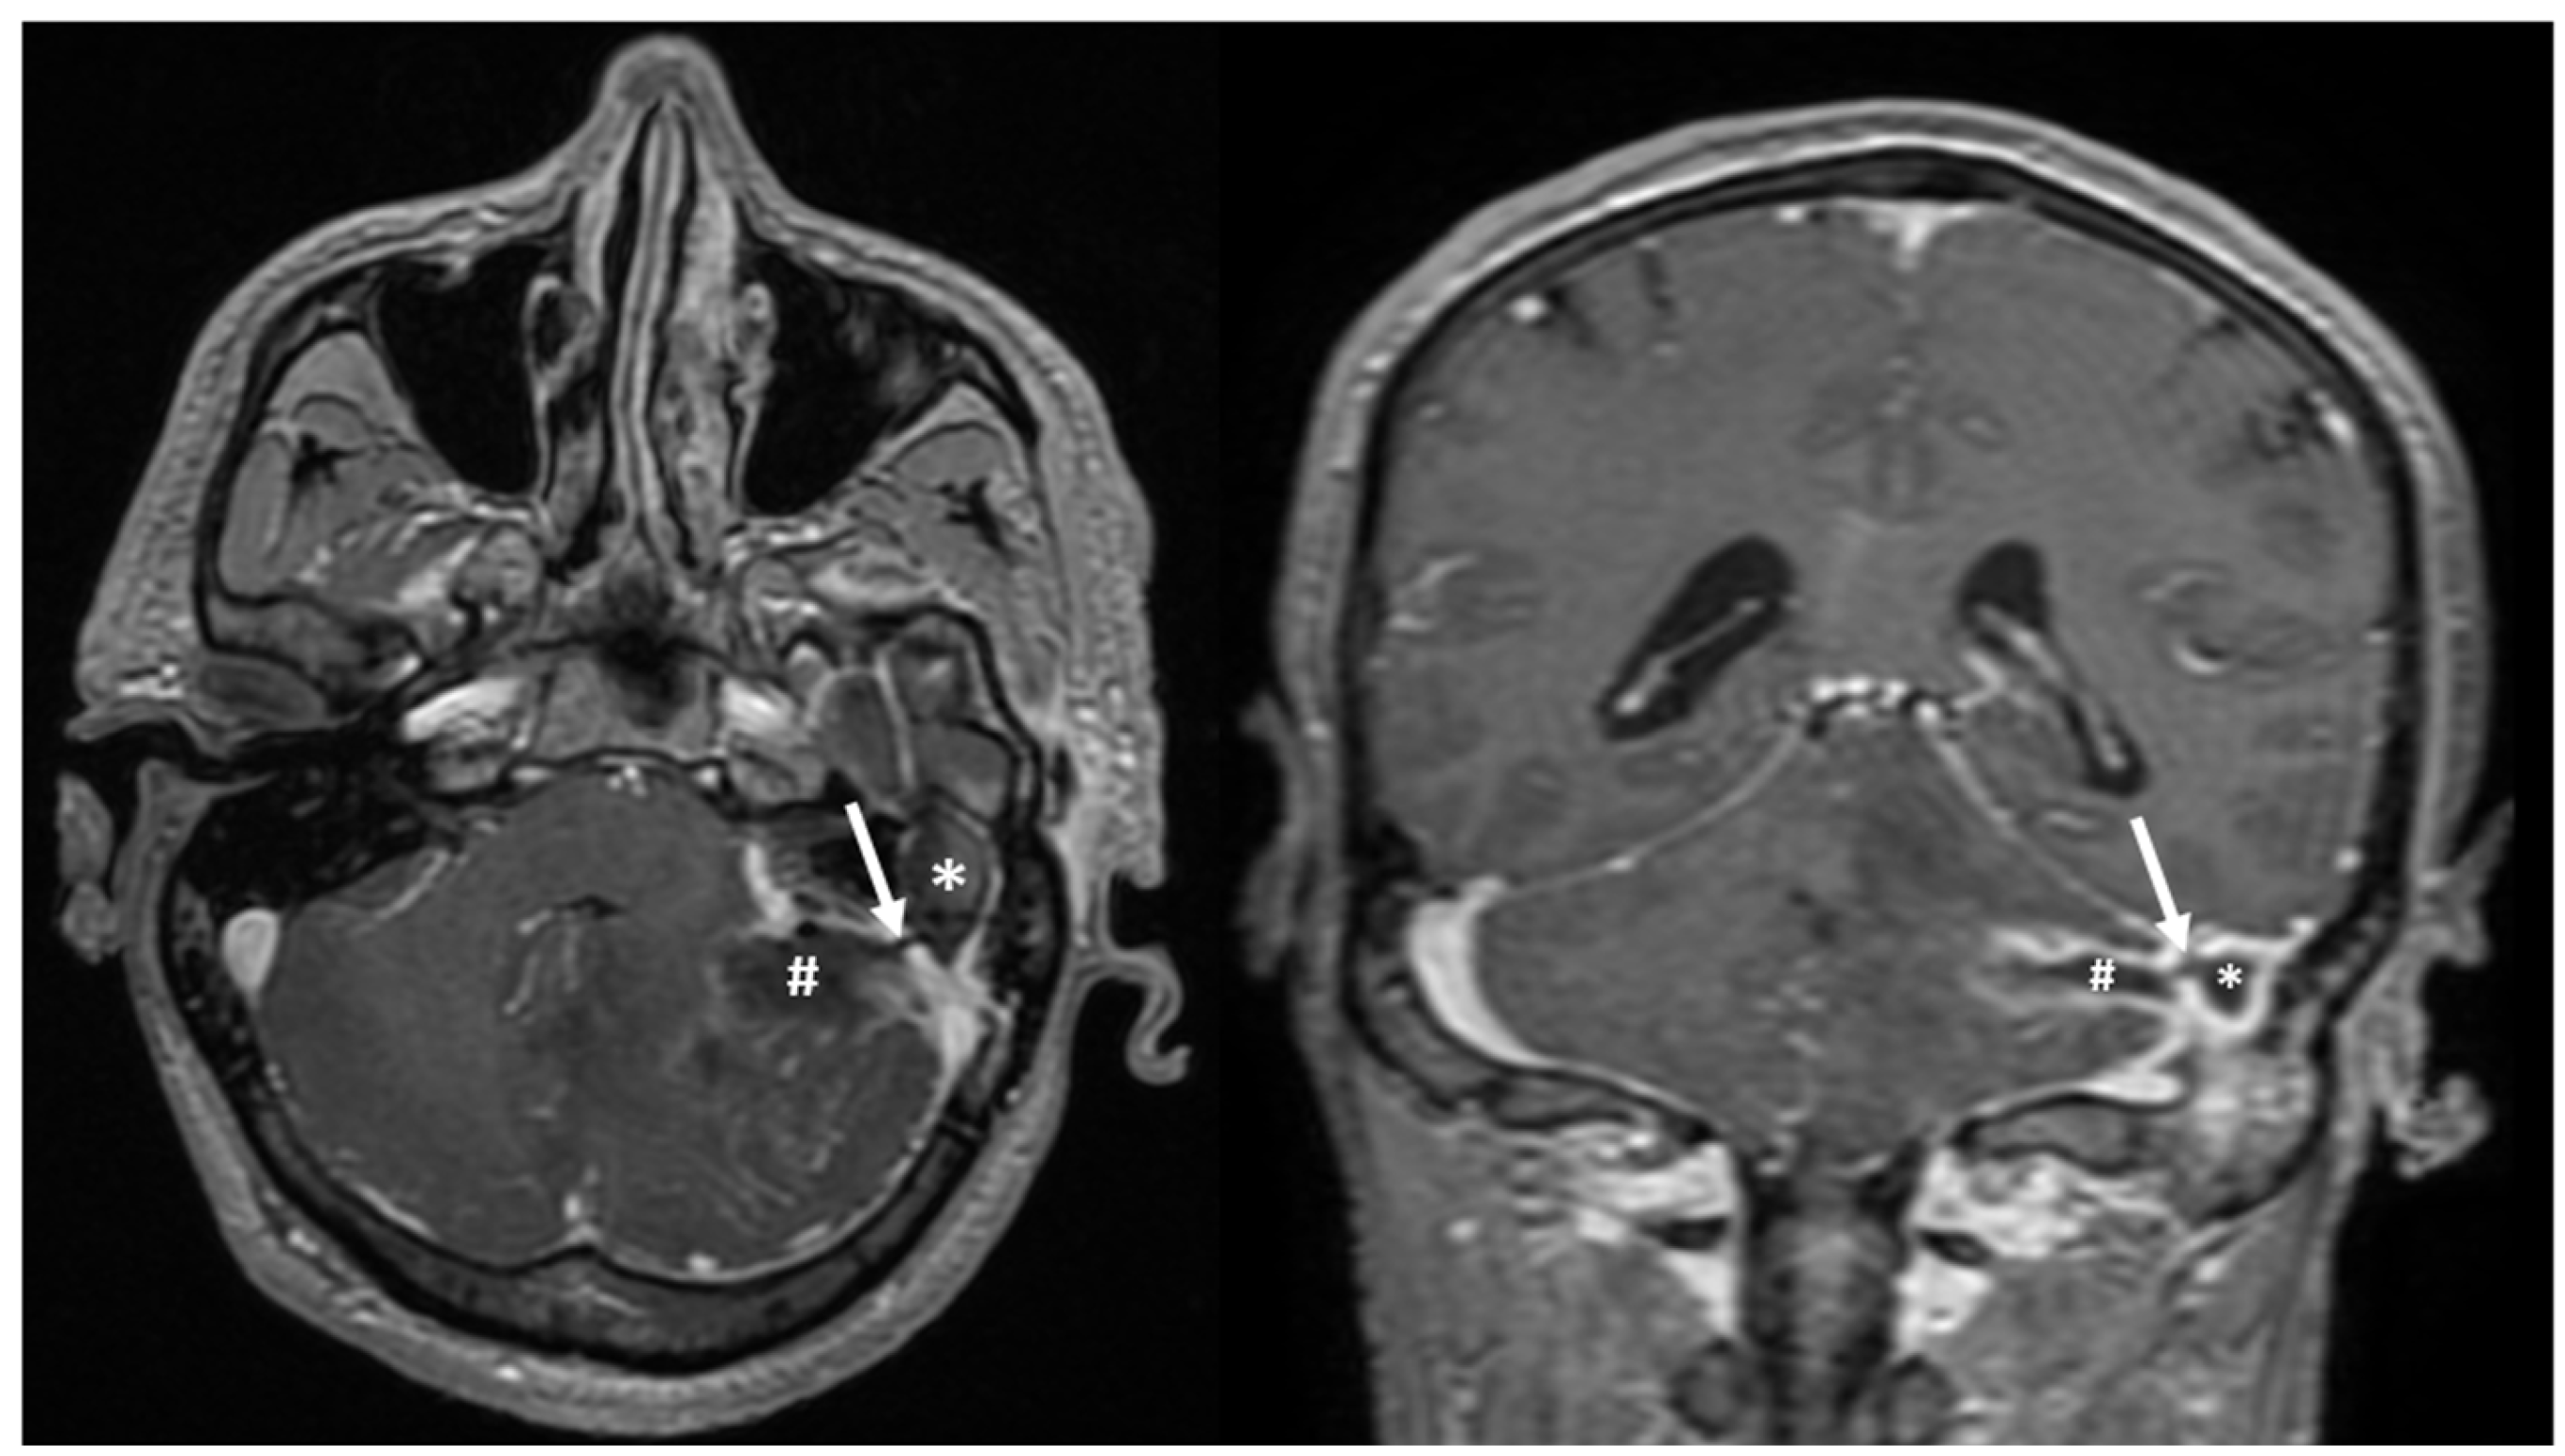

Furthermore, the head MRI scan also revealed soft tissues and inflammation in the left mastoid region, with a connection to the left cerebellar abscess, raising suspicion of a mastoid abscess (Figure 4).

Figure 4. Axial and coronal MRI scan showing the presence of a soft tissue mass in the left mastoid (*), and communication (white arrow) with a cerebellar abscess in the left hemisphere (#); peripheral contrast enhancement can be observed in both lesions.